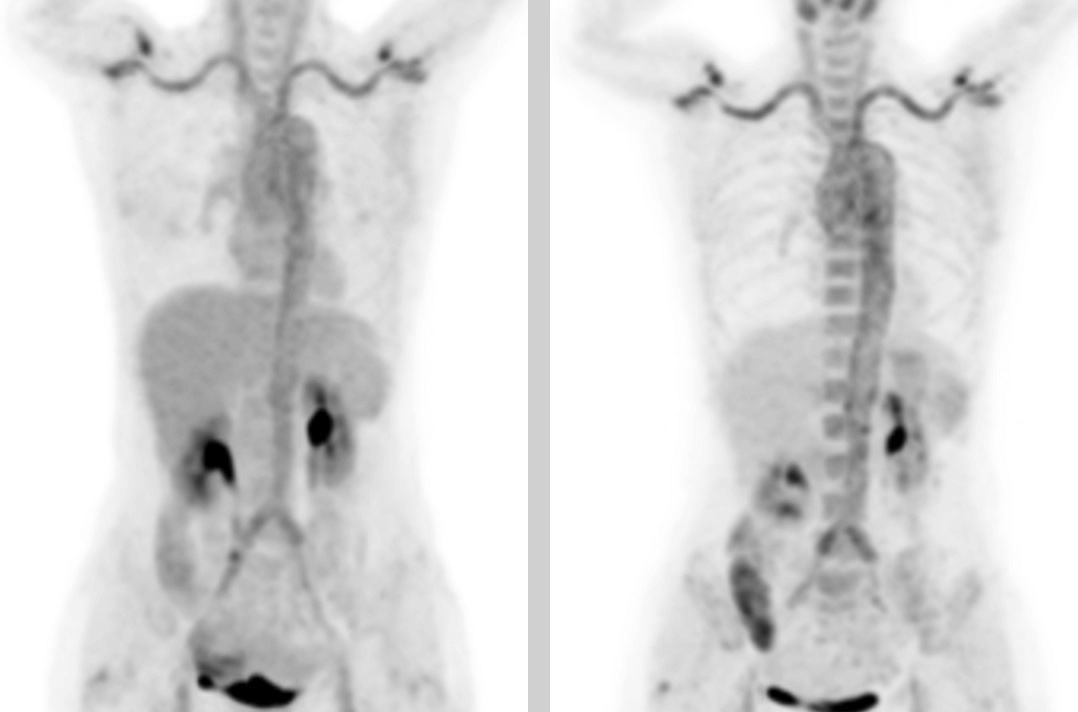

PET/CT 画像では,全身数カ所(両側内頚動脈,総頚動脈,腕頭動脈,両側鎖骨下動脈,腋窩動脈,胸部大動脈,腹部大動脈,両側総腸骨動脈,内腸骨動脈,外腸骨動脈,大腿動脈)に糖代謝亢進を伴う壁厚化を認め,炎症性変化によるものと判断しました。病歴、臨床症状、検査、画像所見を総合してT.A.と診断し、標準的な抗炎症治療を行ったところ、体温が低下し病状が改善しました。

本症例は、T.A.の診断にF-FDG PET/CTを適用した典型的な例です。

F-FDG PET/CTは、T.A.の診断と活動期における疾患活動性を評価することができます。また、全身をスキャンすることにより、病変の領域を把握し、動脈生検の場所を決定する根拠となります。また、治療後の患者さまの反応をモニターすることで、疾患集積部位の代謝亢進を定性的に示すことができます。その半定量的指標SUVmaxは、T.A.の活動性の感度や特異性の検出において、ESRやCRPなどの血清指標を上回り、診断の精度を高めることができます。